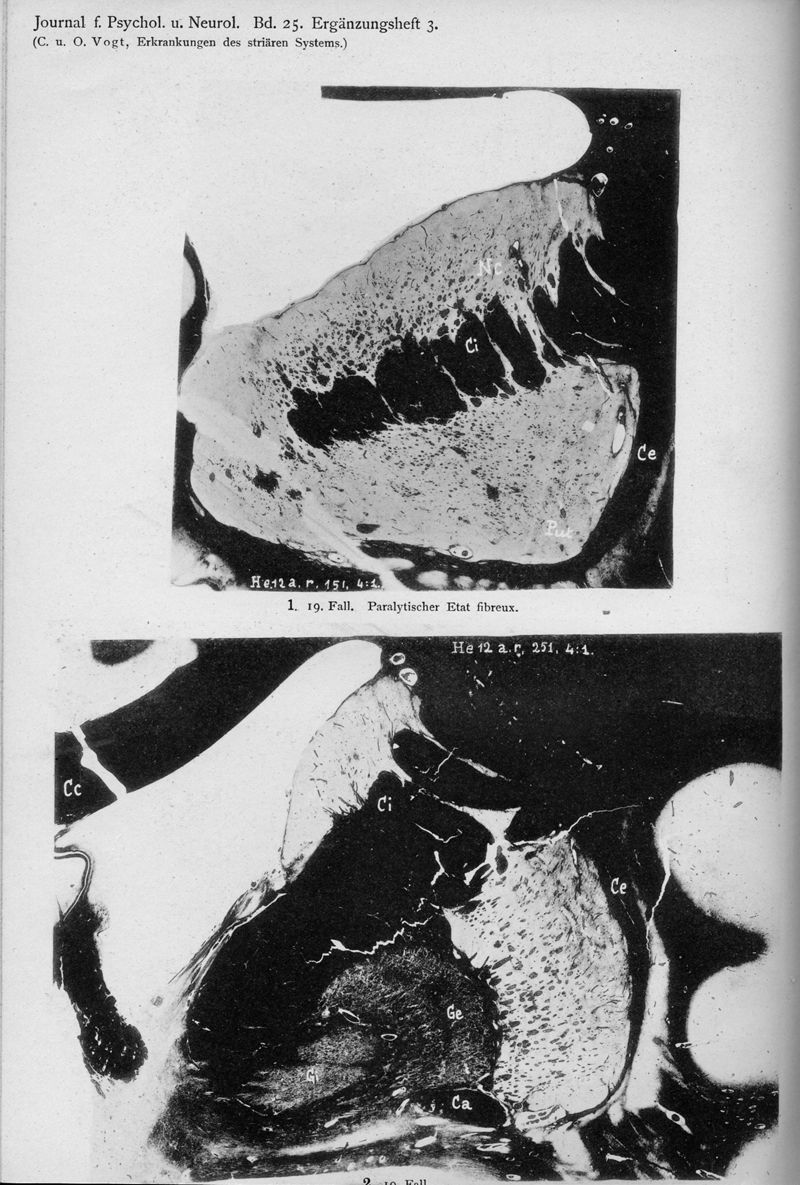

VOGT, Cécile / VOGT, O.

In : Journal für Psychologie und Neurologie,

1920, Vol. 25, pp. 627-846